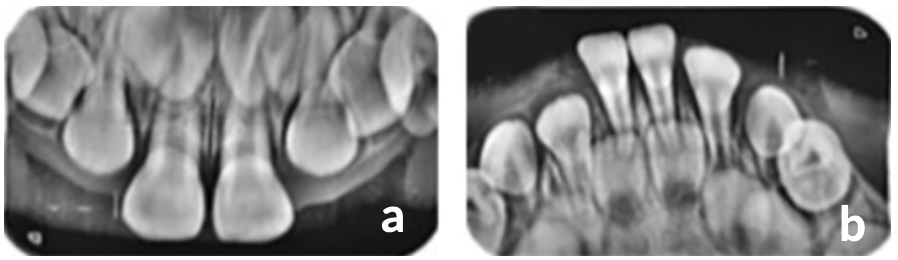

Una vez transcurrido 4 meses desde la primera consulta, se realizó una consulta control y se observó la erupción de incisivos centrales superiores e inferiores, (Figura 1c). Al realizar el examen radiográfico, se encontraron presencia de unidades dentarias 51, 52, 53, 61, 62 y 63 y se observó germen dental de unidades 11 y 21 en radiografía oclusal superior, (Figura 2a). Y en la radiografía oclusal inferior, presencia de unidades dentarias 81, 82, 83, 71, 72, 73 y 84, (Figura 2b).

Dado los hallazgos clínicos y radiográficos encontrados se observó claramente una alteración en la cronología y secuencia de erupción dentaria, puesto que erupciona el primer molar primario antes de terminar la erupción de todo el grupo incisivo, alterando así la secuencia de erupción. Así mismo la cronología se encontró con alteración, ya que la edad de la paciente no coincide con los estándares normales de cronología de erupción, que comienza a partir de los 6 meses de edad. El pronóstico de este caso es favorable, ya que se observó en el examen radiográfico la formación de los gérmenes dentales permanentes y las unidades dentarias primarias próximas a erupcionar, sin embargo se ve afectado el crecimiento de los maxilares, que en el futuro tendrá como consecuencia algún tipo de maloclusión.

Figura 2. Exámenes radiográficos (a. Rx oclusal superior, b. Rx oclusal inferior)